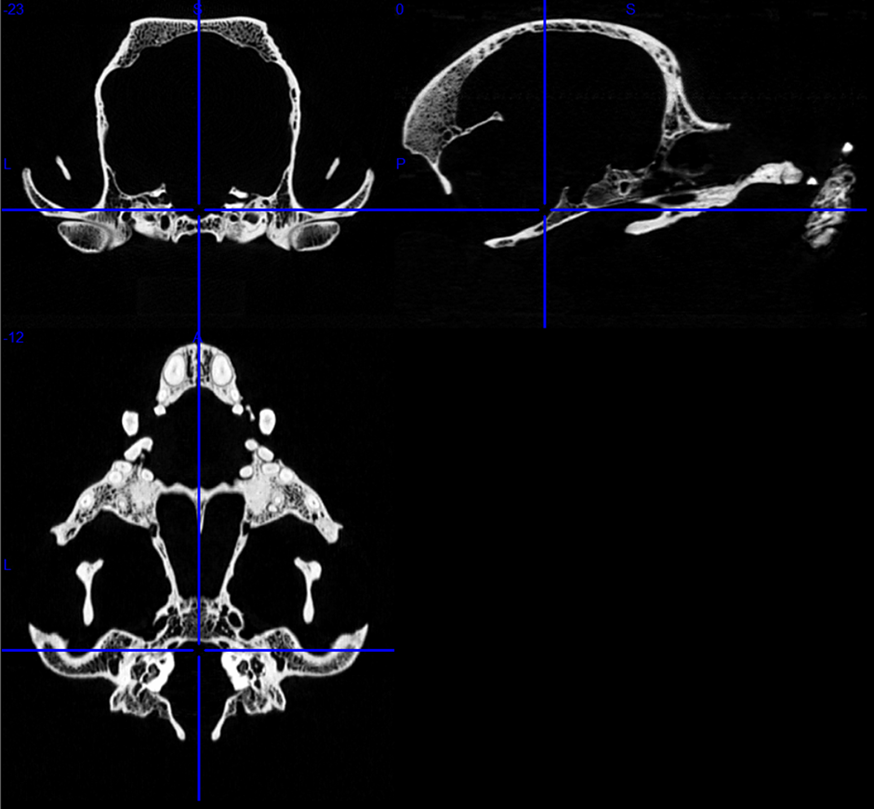

Image: Skull of a Boston terrier on a CT image series. First row: transverse and sagittal views. Second row: dorsal view. Credit: Kálmán Czeibert